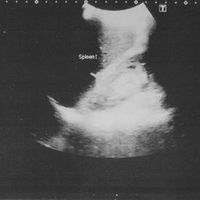

kidney bruise

n y s t a g m u s